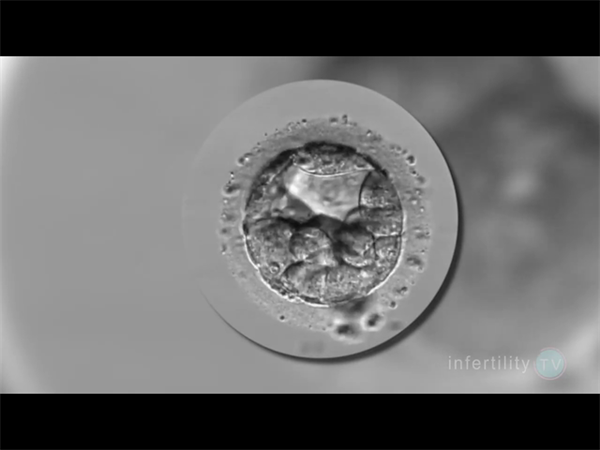

囊胚篩查主要包括三種類型的檢測,PGT-A篩查胚胎的染色體數目是否正常,即非整倍體遺傳學篩查;PGT-M針對特定的單基因遺傳病進行篩查,例如色盲、血友病等;PGT-SR篩查染色體結構變異,例如平衡易位或者羅氏易位,其在一定程度上能減少宮外孕和胎停的可能性。但它們并不能保證篩查完全覆蓋所有可能的遺傳疾病,特別是當這些基因突變屬于未知或新的遺傳疾病時。

盡管囊胚篩查(如PGS/PGD)能夠檢測染色體異常和單基因遺傳病,但其成功率并非100%。單基因遺傳病的種類繁多,目前已知有7000多種單基因遺傳病,其中4000多種已明確致病基因。因此,即使囊胚篩查正常,也不能完全排除其他未檢測到的單基因遺傳病。目前的基因篩查技術主要針對已知的遺傳病基因進行檢測,如地中海貧血、唐氏綜合癥等。然而,許多隱性遺傳病可能尚未被完全識別或列入篩查范圍。即使使用全基因組測序(NGS)技術,也無法檢測到所有潛在的基因突變。